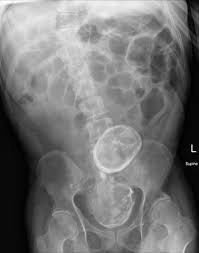

The stones will usually show up white on the x ray.

Kidney stones dog x ray. Kidney stones are a serious medical condition that requires prompt medical treatment. Once your dog has been diagnosed with kidney stones it will be your responsibility to control the condition long term. If kidney stones are suspected your vet will take x rays.

Overview stones of the urinary tract begin as microscopic crystals that aggregate to form stones of variable size and shape anywhere within the urinary system including the kidneys ureters and urethra although stones of the urinary bladder are most common. Cystine stones excessive elimination of cystine in the urine is an inherited disorder of kidney tubular transport that is thought to be the primary cause of cystine stones figure 5. Follow up appointments for urinalysis and or abdominal x rays should be done every 4 6 weeks after treatment initiation to ensure stones are dissolving and new ones are not forming.